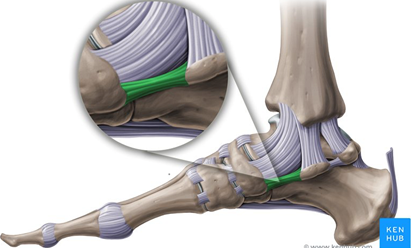

Spring ligament repair or augmentation

The spring ligament (in green) connects the navicular bone and the heel bone (calcaneus) and helps prevent the foot from collapsing in.

In feet that have been poorly aligned for years, this ligament can stretch or tear, causing pain and severe deformity. When appropriate the ligament can be repaired or augmented with an implanted fibre wire to support the arch. It is a procedure that is rarely performed in isolation, but as part of a combination of techniques to correct the foot position.